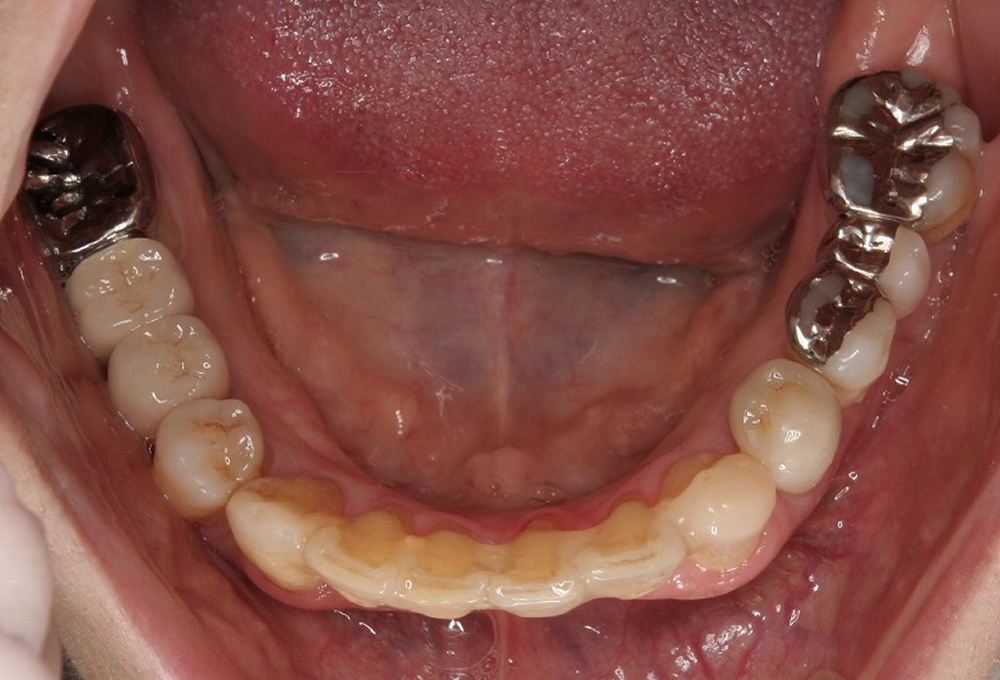

⑪術後 下顎